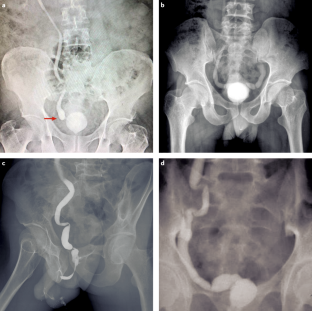

Shah, H. U., Sannananja, B., Baheti, A. D., Udare, A. S. & Badhe, P. V. Hysterosalpingography and ultrasonography findings of female genital tuberculosis. Diagn. Interv. Radiol. 21, 10–15 (2015).

Ahmadi, F., Zafarani, F. & Shahrzad, G. Hysterosalpingographic appearances of female genital tract tuberculosis. I. Fallopian tube. Int. J. Fertil. Steril. 7, 245–252 (2014).

Ahmadi, F., Zafarani, F. & Shahrzad, G. S. Hysterosalpingographic appearances of female genital tract tuberculosis. II. Uterus. Int. J. Fertil. Steril. 8, 13–20 (2014).

Farrokh, D., Layegh, P., Afzalaghaee, M., Mohammadi, M. & Fallah Rastegar, Y. Hysterosalpingographic findings in women with genital tuberculosis. Iran. J. Reprod. Med. 13, 297–304 (2015).